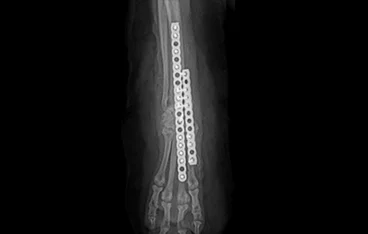

PLATE 수술 후